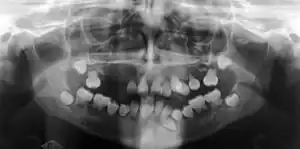

| Preoperative panoramic radiographs showing features of dentin dysplasia type I | |

Radiographic feature

In other words, affected primary teeth usually have abnormal shaped or shorter than normal roots. “Crescent/half-moon shaped” pulp chamber remnant in permanent teeth can be seen on x-rays. The roots may appear to be darker or radiolucent/pointy and short with apical constriction. Dentine is laid down abnormally and causes excessive growth within the pulp chamber. This will reduce the pulp space and eventually cause incomplete and total pulp chamber obliteration in permanent teeth.[12][13] Sometimes periapical pathology or cysts can be seen around the root apex.[11] Most cases of DD associated with peri-apical radiolucency/ pathology have been diagnosed as radicular cysts, but some of them have been as diagnosed peri-apical grauloma instead.[14]

Radiographic features

In coronal type, teeth show normal roots containing enlarged pulp with abnormal extensions towards the roots, which is often described as “thistle tube” shaped on dental radiographs. As well as this, numerous pulp stones can be often found in the pulp chambers due to abnormal calcifications.[15] In primary teeth, the pulp chamber is usually completely obliterated but in permanent teeth, the pulp may become partially obliterated after eruption.[11]